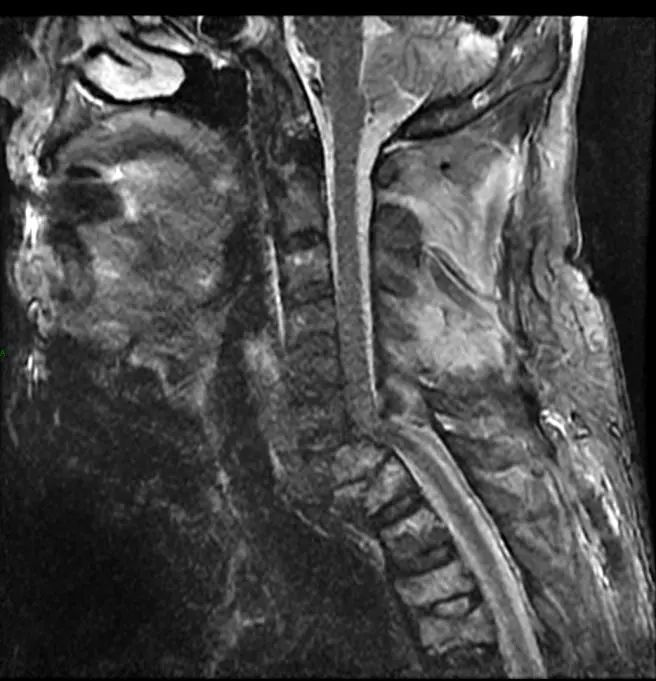

术前MR提示:C7椎体完全脱位,颈胸椎多发骨折

经过颅骨牵引后,在孙欣副主任的带领下,团队成员彭智恒博士、李广盛博士、黄维渊博士以及程龙医师在充分研究患者骨折脱位情况,结合患者身体条件,为患者实施了颈椎前路加后路联合手术。该部位手术难度极大,术中由于肩关节遮挡,术中DR难以准确指示胸1、胸2椎体置钉位置,需要术者全凭手感置钉。孙欣副主任凭借丰富的手术经验,加上麻醉科、手术室团队的密切配合,手术十分顺利。术后复查显示脱位的颈椎已完全复位,同时未造成神经功能二次损伤。